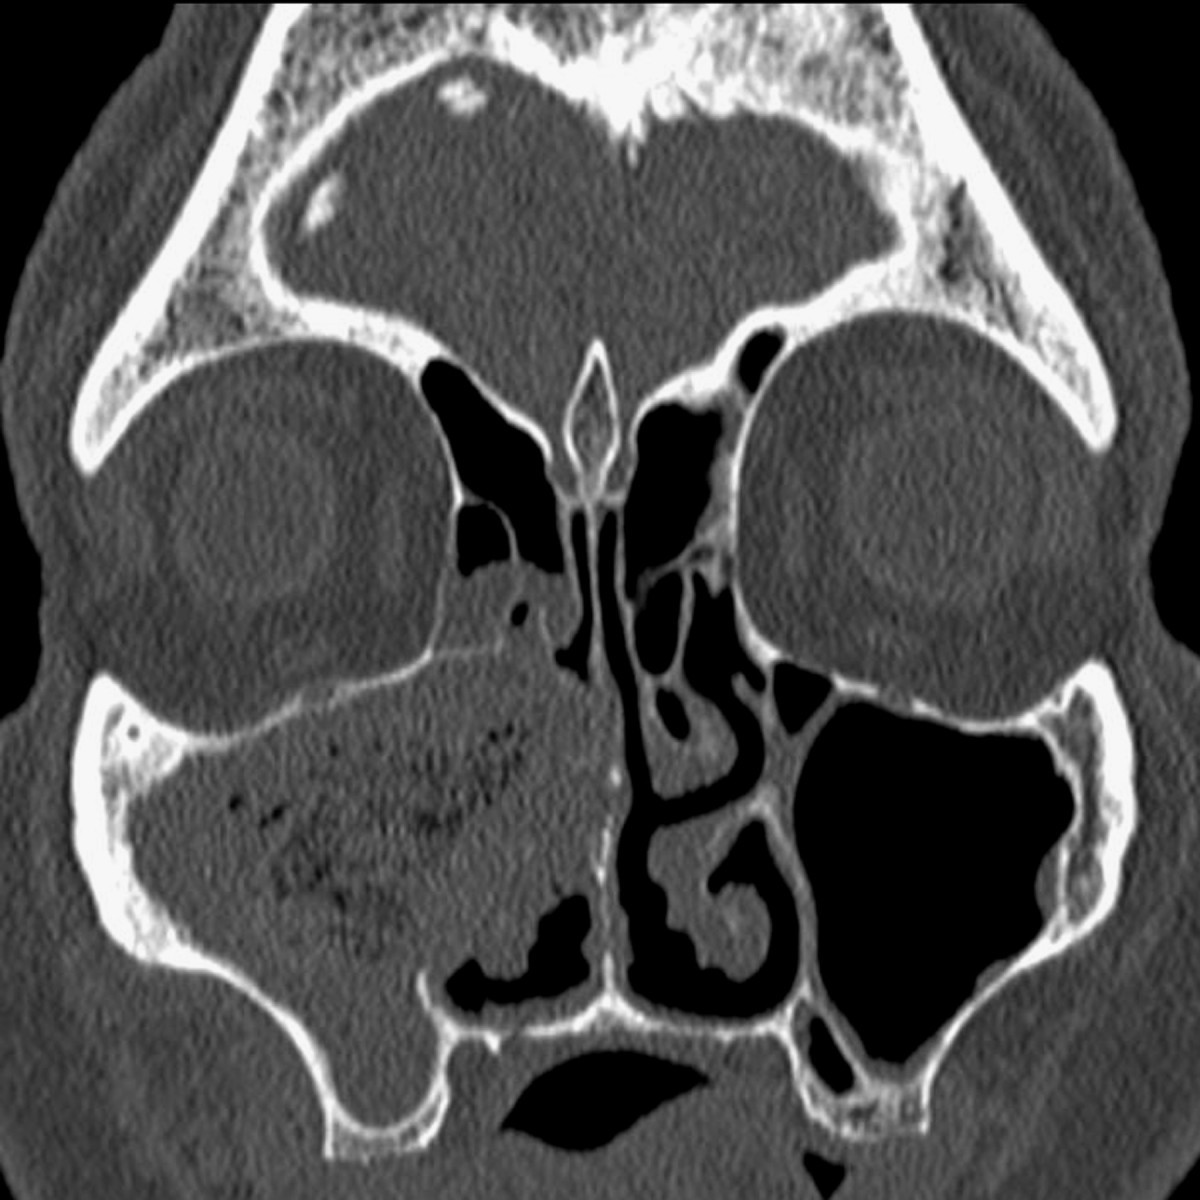

Acute sinusitis lasts up to four weeks. when symptoms persist for more than 12 weeks, you may have chronic sinusitis. but some cases of chronic sinusitis can develop subtly, without a preceding viral infection. in chronic sinusitis, the lining of sinus cavities, called mucosa, becomes inflamed and swollen. Asam urat yang dihasilkan akan larut pada darah, disaring oleh ginjal lalu di buang melalui urin. terkadang proses ini terganggu, dimana tubuh menghasilkan terlalu banyak asam urat atau waktu tubuh tidak bisa menyaring asam urat dengan baik. sebagai akibatnya asam urat tinggi dalam darah atau dianggap menggunakan istilah hiperurisemia. 15 nov 2017 if conditions persist past three months, it's considered chronic. chronic sinusitis by the numbers. doctors split people with the disease into two . Asam urat umumnya larut dalam darah & akan disalurkan ke ginjal. ginjal lalu akan mengeluarkan kelebihannya secara rutin melalui urin dan feses agar kadar asam urat months 2 sinusitis dalam darah tetap normal. tetapi, terkadang kadar asam urat sanggup terlalu tinggi pada tubuh. hal ini bisa ditimbulkan sang gangguan fungsi ginjal sehingga ginjal nir bisa.

Batas bawah asam urat normal pria yakni 2 mg/dl dengan batas atas 8,5 mg/dl, sedangkan perempuan mempunyai batas bawah asam urat dua mg/dl & 8 mg/dl sebagai batas atas. saat nilai asam urat ini berada dalam batas yang rancu, maka akan timbul aneka macam gangguan kesehatan. Autoimmune hepatitis, formerly called lupoid hepatitis, is a chronic, autoimmune disease of the liver that occurs when the body's immune system attacks liver cells, causing the liver to be inflamed. common initial symptoms include fatigue or muscle aches or signs of acute liver inflammation including fever, jaundice and right upper quadrant. Common causes of chronic sinusitis include: 1. nasal polyps. these tissue growths can block the nasal passages or sinuses. dua. deviated nasal septum. a crooked septum — the wall between the nostrils — may restrict or block sinus passages, making the symptoms of sinusitis worse. tiga. other medical conditions. the complications of conditions such as cystic fibrosis, hiv and other immune system-related diseases can lead to nasal blockage. 4. respiratory tract infections. infections in your respirat 27 mei 2020 kemudian juz butir pare beserta madu & air. berikut manfaat juz pare bagi kesehatan, dirangkum liputan6. com menurut aneka macam sumber, rabu (27/lima/ .

11 jun 2020 jangan konsumsi pare hiperbola. pahit, ini 4 manfaat pare buat kecantikan · 10 manfaat juz pare buat kesehatan, tangkal diabetes. Dec 23, 2019 · a sinus infection, a. k. a. sinusitis, can be either a viral or bacterial infection. the term “sinusitis” simply means that there’s irritation in your sinuses, which make up the lining around. Chronic sinusitis occurs when the spaces inside your nose and head (sinuses) are swollen and inflamed for three months or longer, despite treatment. this common condition interferes with the way mucus normally drains, and makes your nose stuffy. breathing through your nose may be difficult, and the area around your eyes might feel swollen or tender. chronic sinusitis can be brought on by an infection, by growths in the sinuses (nasal polyps) or swelling of the lining of your sinuses. also calle